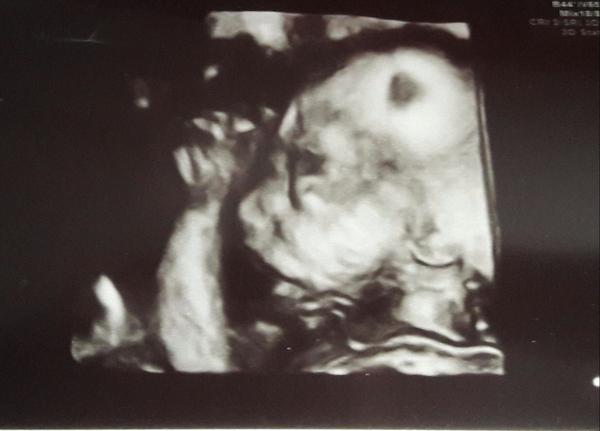

@sasenka04 😍😍😍😍😍😍😍😍😍 dievčatko 💪👌👍❤💕 waw 🙂 teším sa s Tebou veľmi 😇 A už máš aj nejaké meno vymyslene ?

@zuzuliena1 no na tej druhej fotke, co si sem dala vyzera ako maly nasraty chlapcek - zlate aj tak...No nech je to to, po com Tvoje srdce tuzi, prajem Ti to 😉...A samozrejme, nech ste obaja zdravi, to je naj 😘